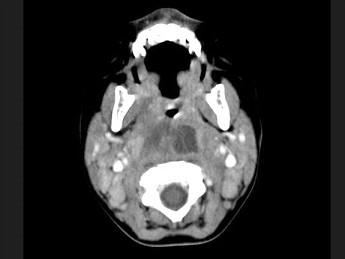

问题 10个月大的婴儿,发热,曾患中耳炎,CT扫描如图所示,请选择正确的描述或诊断 ( )

选项 A、考虑为咽后壁脓肿 B、考虑为咽后壁寒性脓肿 C、其内密度不均 D、颈椎骨质未见明显异常 E、咽后壁软组织肿胀

答案 ACDE